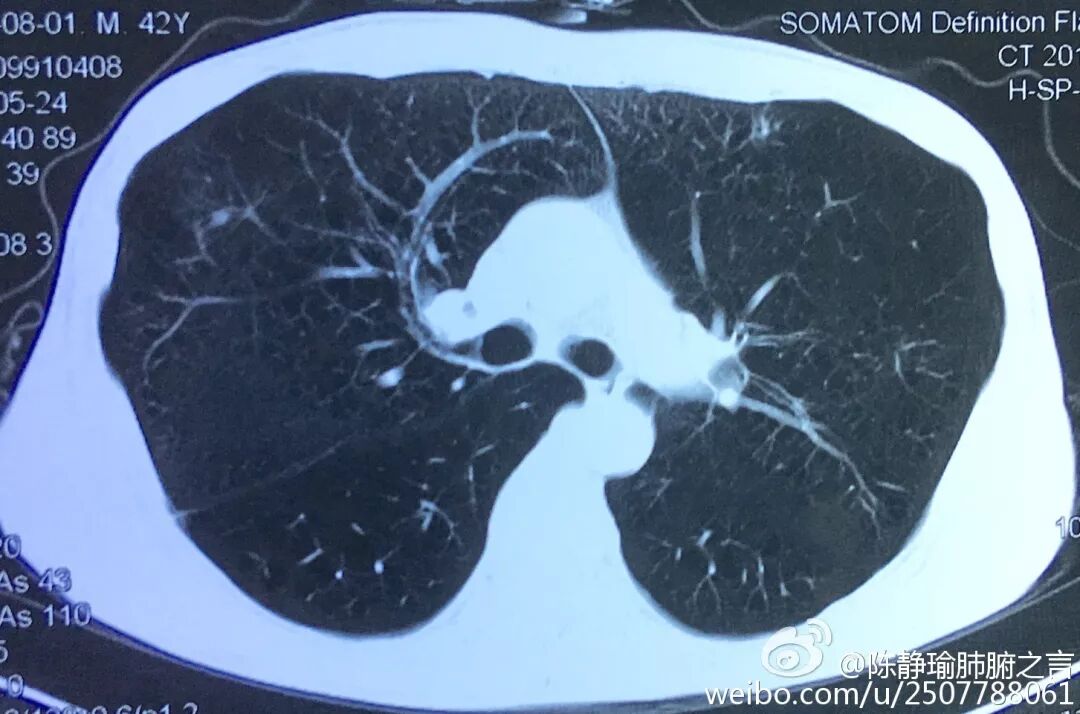

这是2016年陈静瑜在他的微博 @ 陈静瑜肺腑之言 里发的一条呼吁戒烟的内容。文字配上了七八张手术摘除的黑肺的图片,大片的肺上布满了密密麻麻恶心的「黑色沉积物」,看得人惊心动魄。然而无论是他的发微博还是微信朋友圈,像这样的专门「晒」出术后摘除的已严重变黑的肺,大致一数就有好几十条,每一条无一例外的都配上了一段劝告公众戒烟的文字。

「我发的最多的是那些病变肺的片子。我尤其喜欢发『黑肺』、『尘肺』,我的目的很明确,就是要宣传禁烟,宣传关注尘肺病人。」 陈静瑜说。

「戒烟就靠意志力,只要他们意识到吸烟会导致肺变成这样,很快就能成功戒烟。那怎么才能让所有人都意识到这一点呢?我就把从手术台上切下来的病变肺全往微博上『晒』,我不怕别人怎么说我,也许我这么做在医生圈子里就是第一个。我当初开微博也是在同行鼓动之下开的,2012年到现在七年了,我发了几千条微博,贴出的病肺照片有上百张,总会有点宣传效果吧。」

陈静瑜始终相信「恶性刺激」有效果。「我之所以公布的片子基本都是黑肺、肺部肿瘤、肺部纤维化,就是要告诉大家吸烟是很重要的诱因。」陈静瑜说,「劝他们戒烟,最直接的办法就是给他们做体检看肺部的病变情况,不断地给他们看这些『重口味』照片。戒烟就靠意志力,只要他们意识到吸烟会导致肺变成这样,很快就能成功戒烟。」